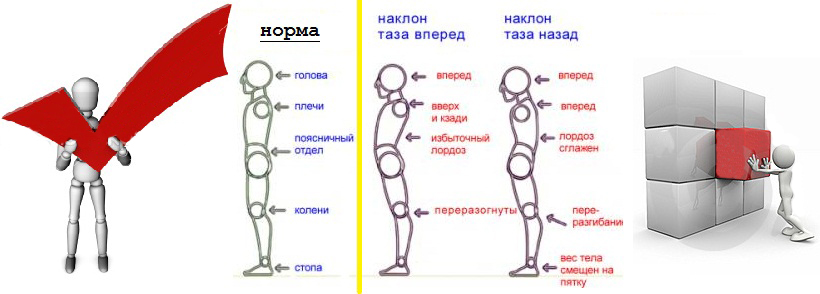

Анатомия и упражнения: Перекос таза и мышцы бедра